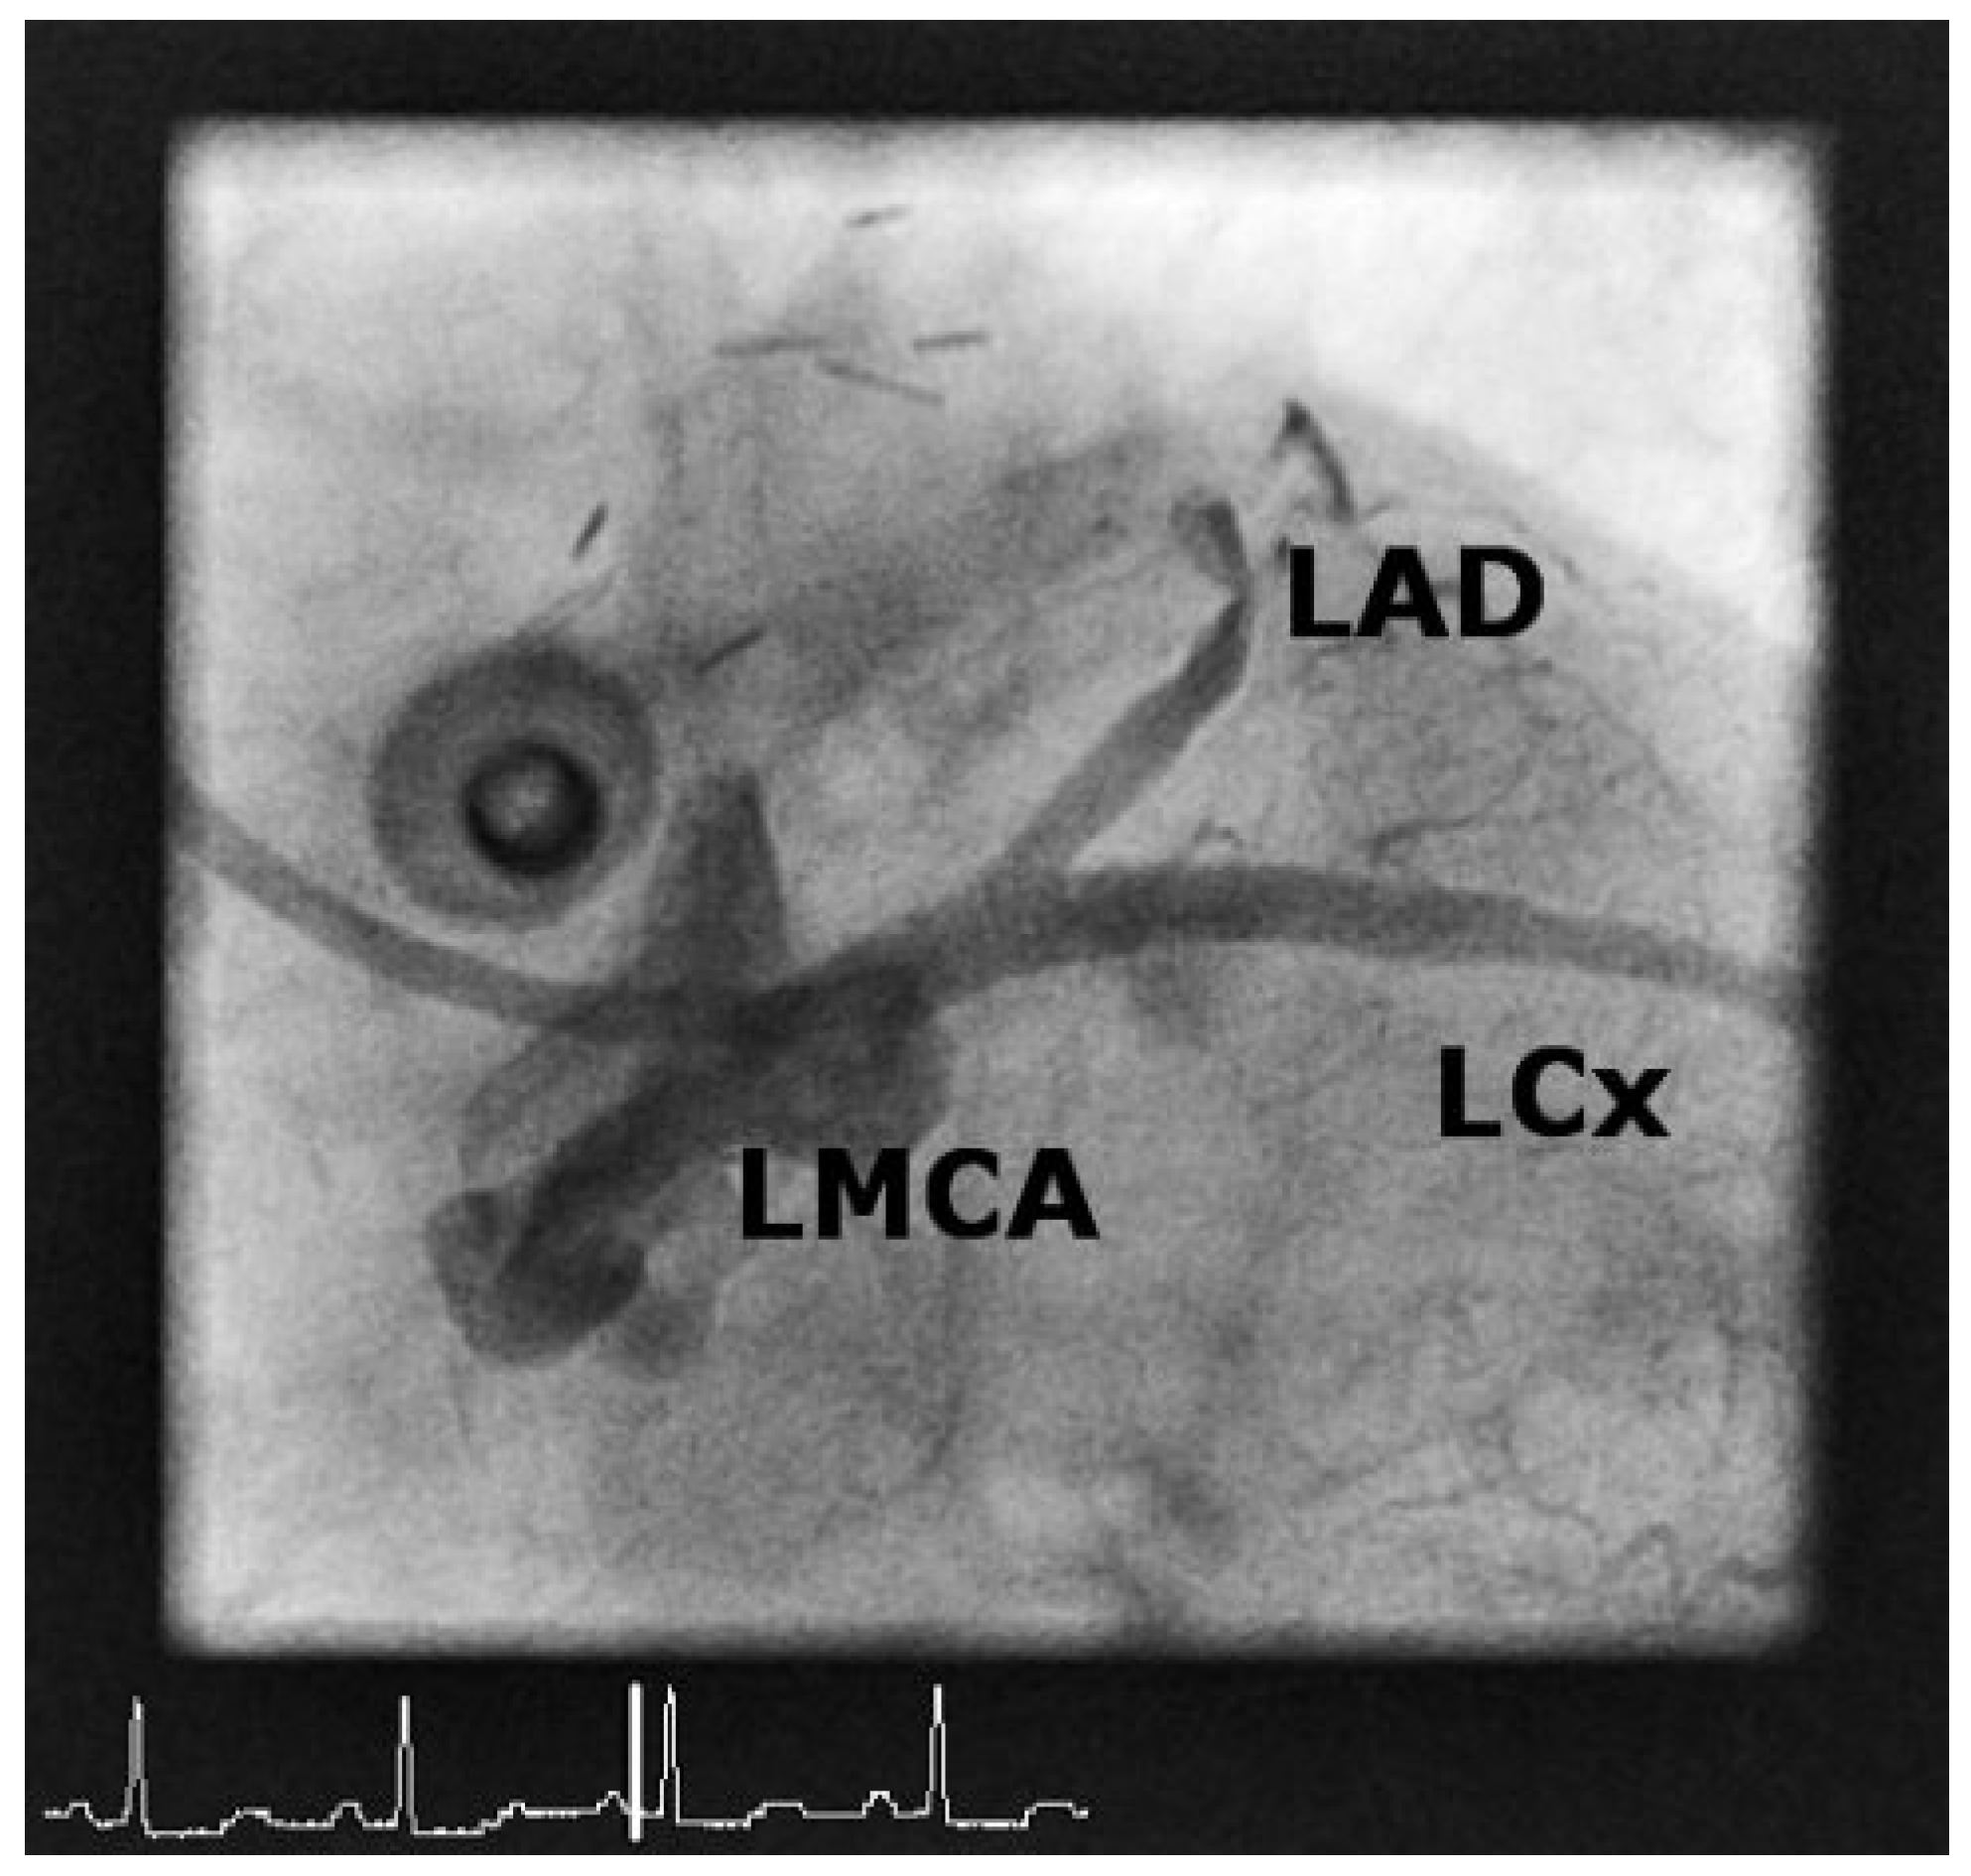

Case 1

Case2